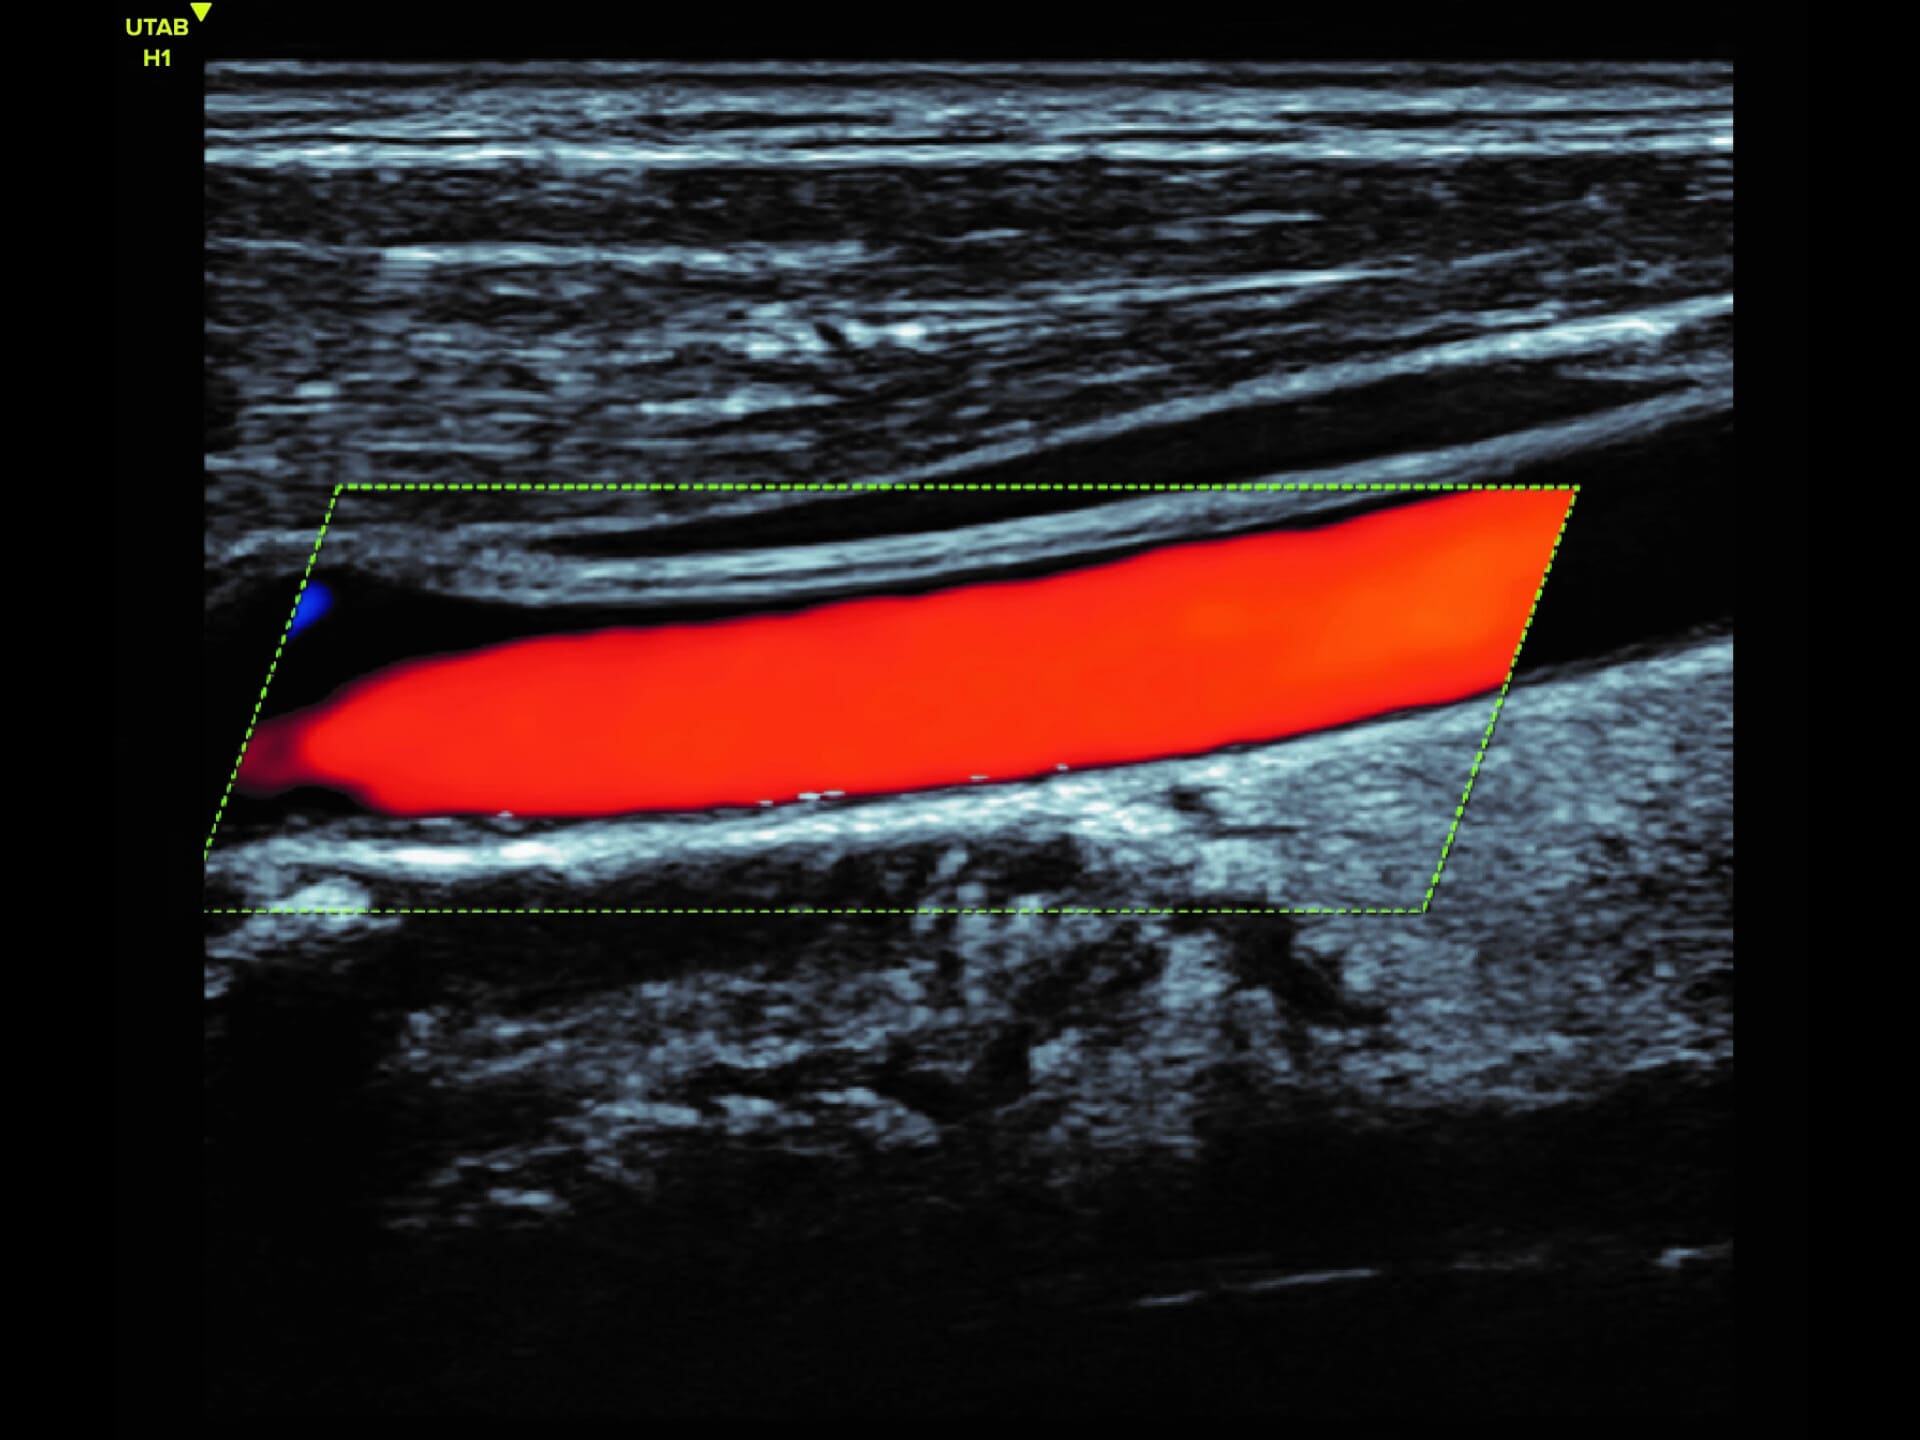

L9-2 Linear Array Probe

Crystal-clear imaging for muscles, vessels, and soft tissues—perfect for targeted exams and real-time procedures.

The L9 – 2 is a linear array ultrasound probe featuring advanced wideband technology, which enables a broader frequency range for superior image resolution and clarity. This enhanced imaging capability makes it ideal for a range of clinical applications.

The L9 – 2 is a linear array ultrasound probe featuring advanced wideband technology, which enables a broader frequency range for superior image resolution and clarity.

This enhanced imaging capability makes it ideal for a range of clinical applications.

Applications:

Musculoskeletal, Thyroid, Small Parts, Pediatrics, Peripheral Vascular, Breast, Obstetrics

B-mode, HI, XBeam, Speckle Reduction, Virtual Convex, M-mode, PW (Update, Duplex, Triplex, HPRF), CFM, PD